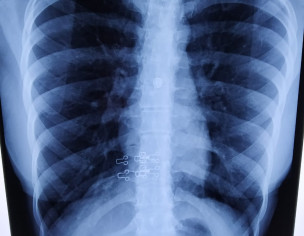

Doctor i am having cough since 20 days it's not that much severe it starts at night for sometime and at days i have nothing. I normally have dust allergy. The picture of my chest xray is attached.

Attach Photo here: